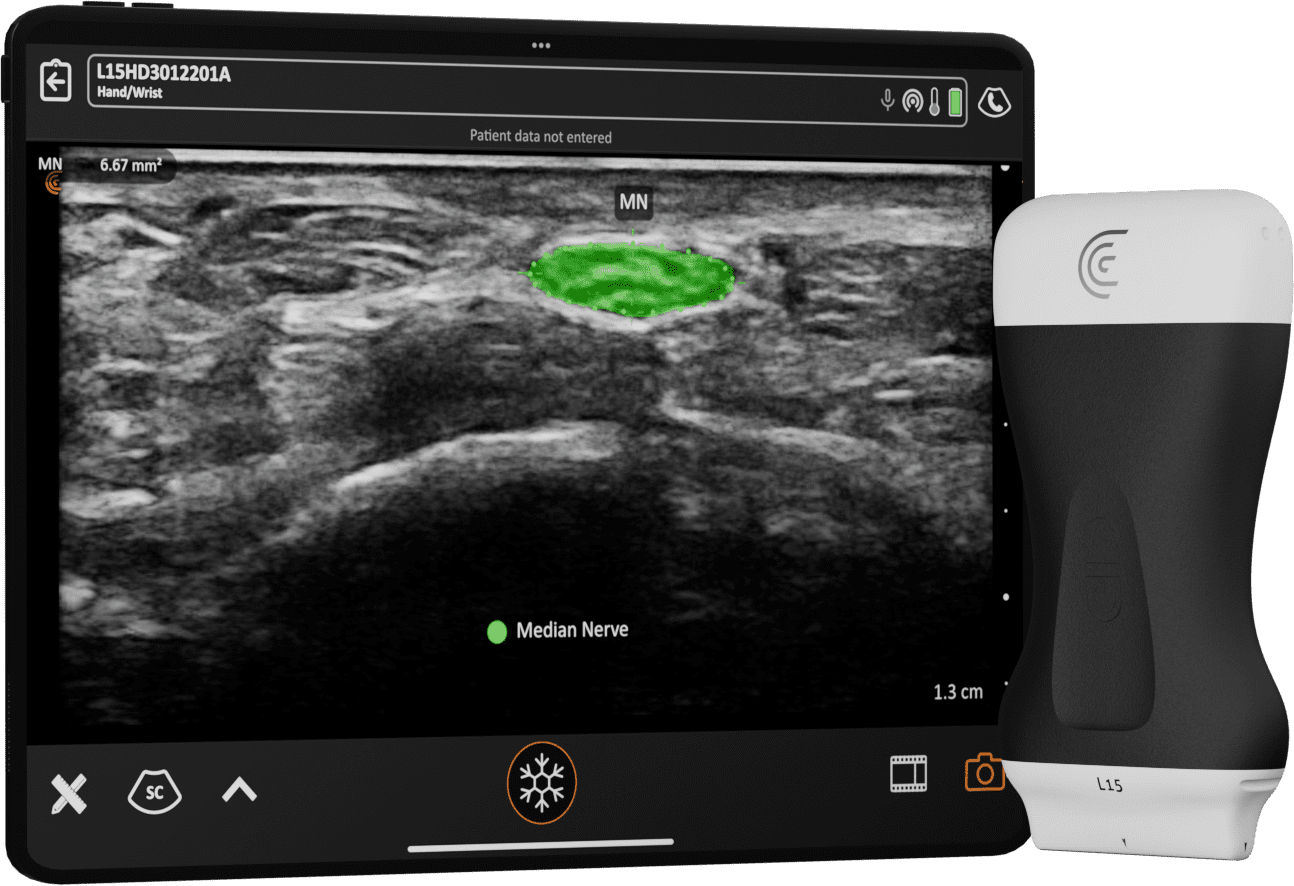

Clarius Intelligence combine des outils intelligents et l'automatisation pour rationaliser le balayage et vous permettre de rester concentré sur votre patient.

IA pour Rationaliser

Accélérez les workflows avec l'automatisation intelligente et le guidage des aiguilles.